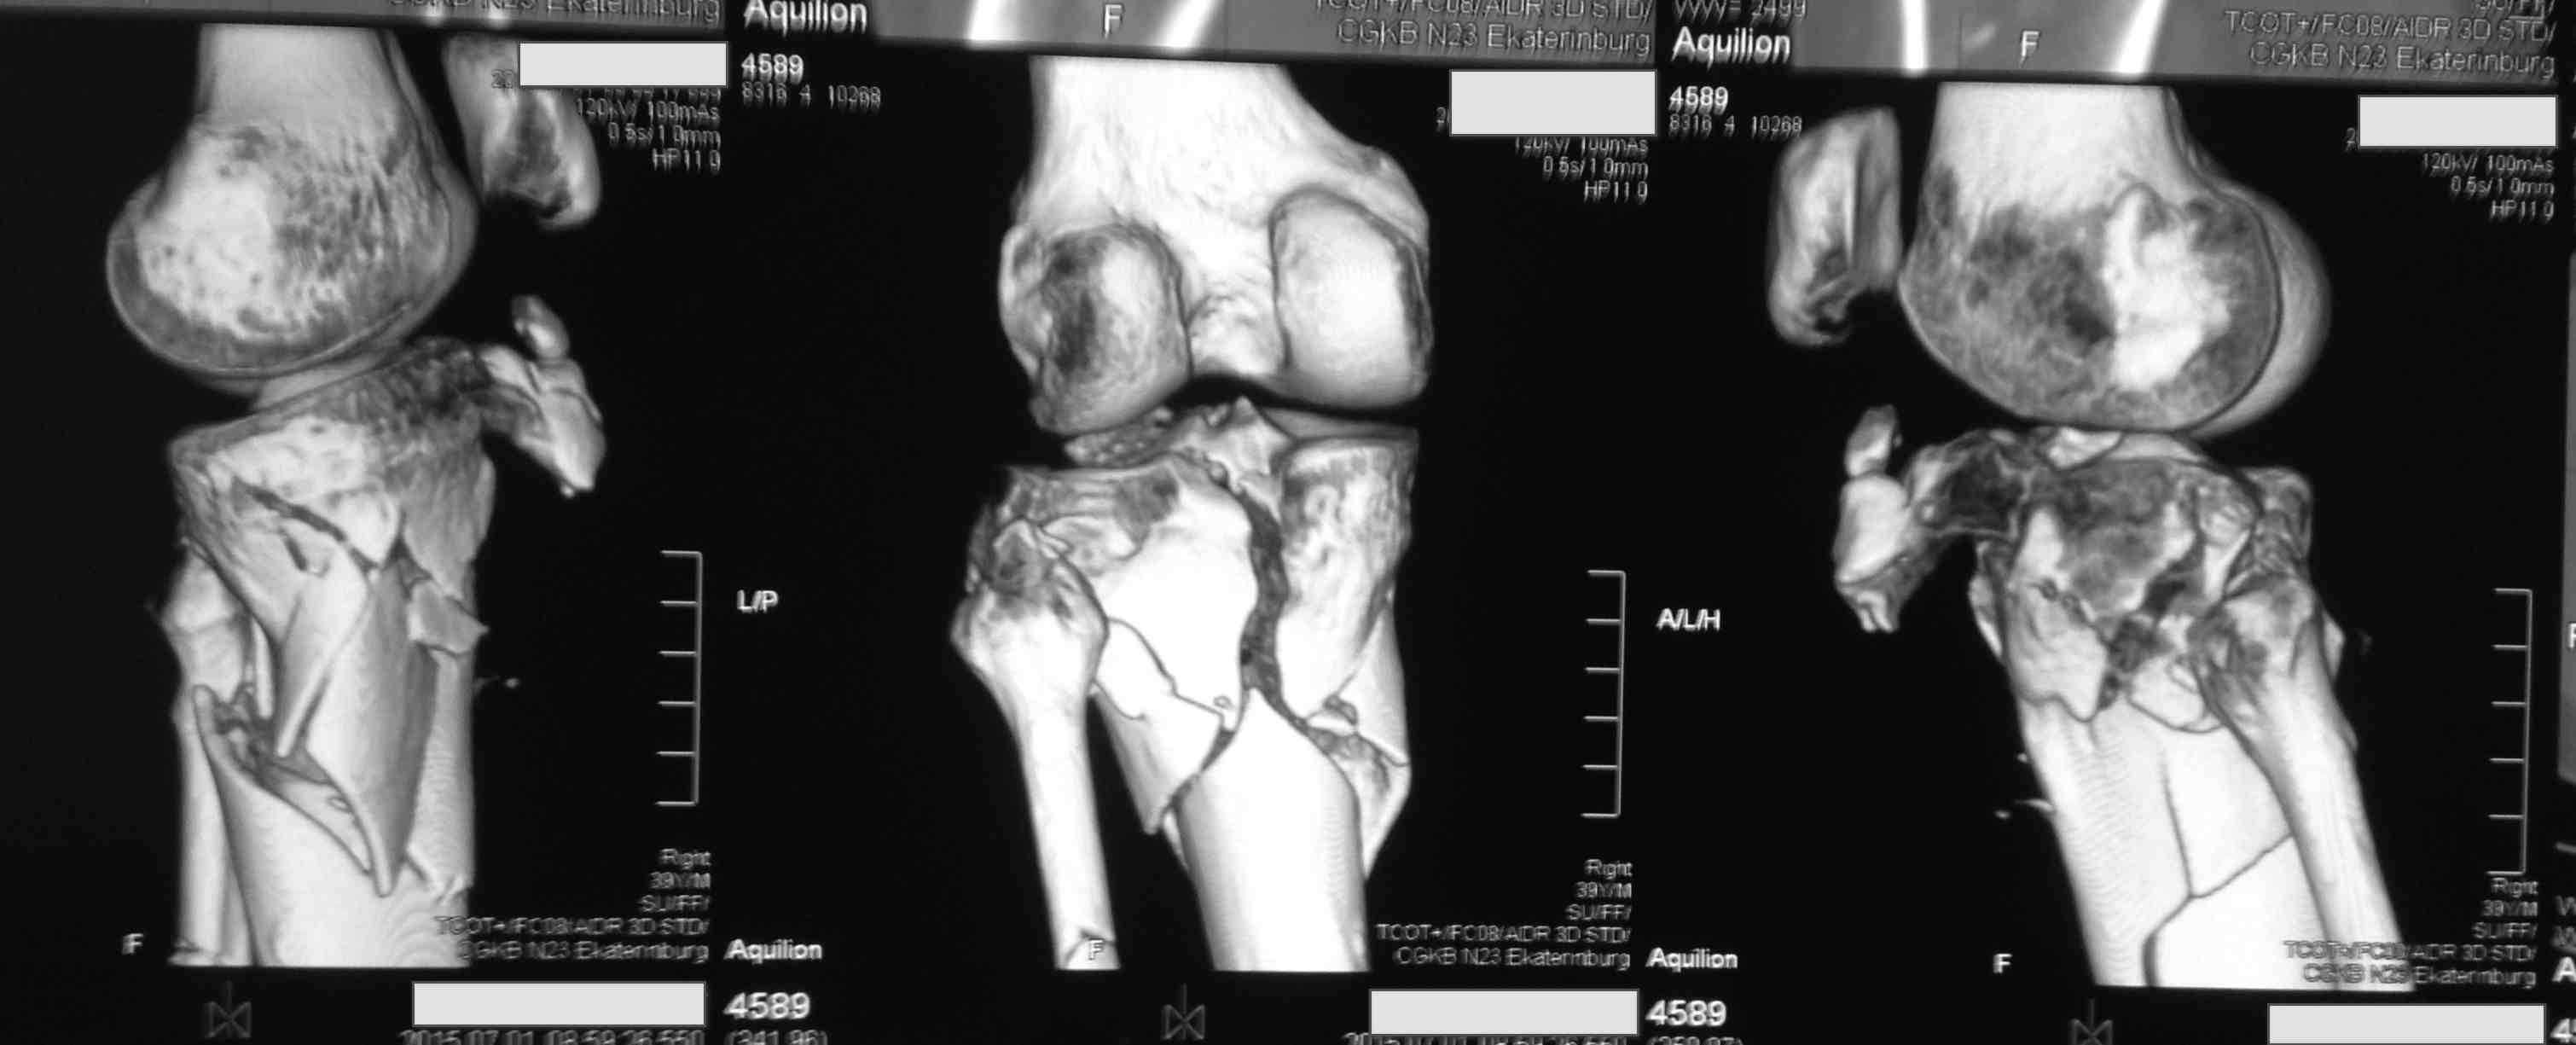

[Ortho] перелом проксимальной тибии + вывих бедра

Высокоэнергетическая травма около недели назад, мужчина 39 лет

По месту поступления вывих бедра вправлен, ПХО раны открытого перелома

б/б кости, скелетное вытяжение. В настоящее время рана заживает неплохо,

небольшое количество серозно-геморрагического отделяемого, состояние

мягких тканей неплохое. Планируем остеосинтез плато из 2-х доступов по

заживлению раны.

1 смущает фрагмент плато в проекции раны, насколько удобно его будет

ловить, попробовать полечить в аппарате + винты

закрыто?

2 часть задней стенки в суставе, такое впечатление, что она больше ямки

и подвывихивает сустав или это ошибочное впечатление?

3. насколько целесообразно искать этот фрагмент во впадине и пытаться

засинтезировать задний край при наличии довольно выраженного FAI?